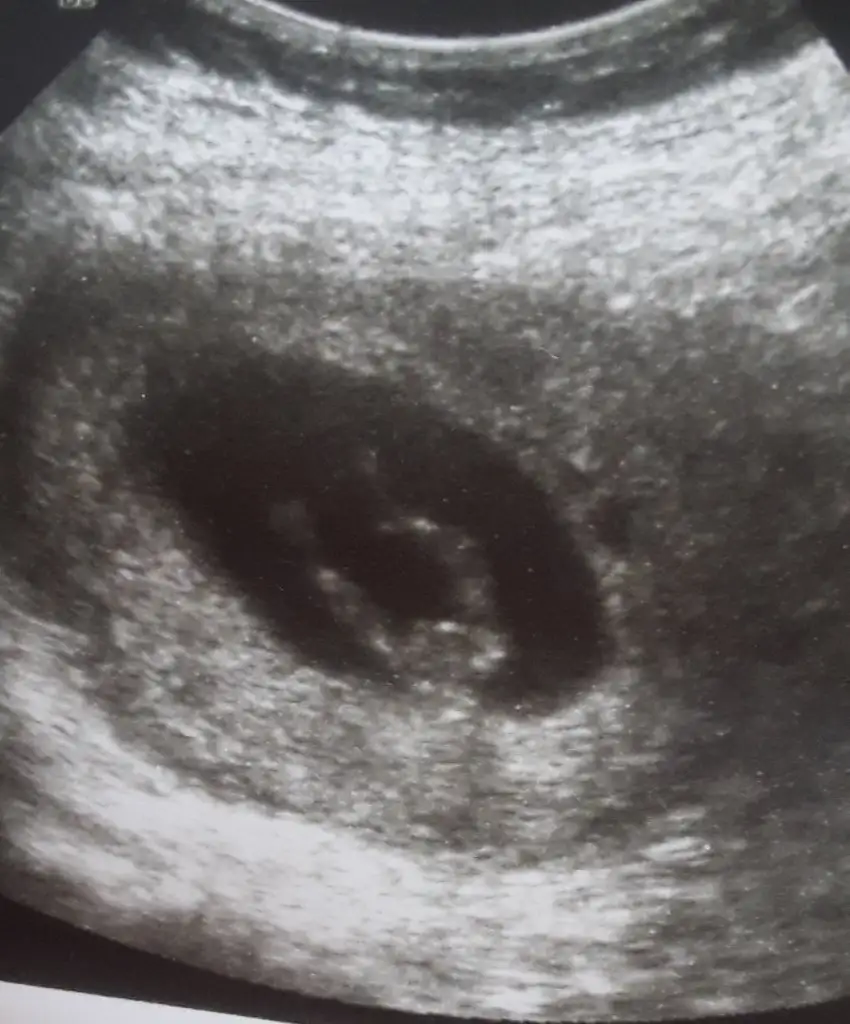

Burada kız gibi zaten 12 13 hafta usg istemiştim burada kaç hafta usgHer iki doktor farkli soyledi cinsiyetini 10ngun sonra kesin soyleriz dedi son fotograflar yeni bacak arasi net dikattli bakinca belki fikrin netlesir belki canim![]()

Usg net değil kaç hafta usg 12 13 de paylaşırsınız emin değilim sanki kızKızlar bizede tahminde buluna bilir misiniz vajinal ultrason![]()

11 hafta 4 gun burda erkekege benzetmistiniz daha once ☺Burada kız gibi zaten 12 13 hafta usg istemiştim burada kaç hafta usg![]()

Karından bakıldı ama bunda. Oncrki 5haftata erkek demistin izKarından bakıldı ise kız siz yinede 11 12 13 hafta nub için usg paylaşın

Kese konumu tutmuyorda siz 11 12 13 hafta paylaşınKarından bakıldı ama bunda. Oncrki 5haftata erkek demistin iz![]()